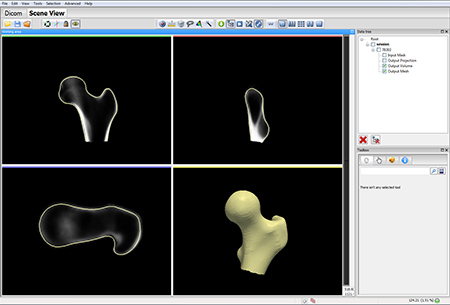

Двухэнергетический многосайтовый остеоденситометр с программой "все тело", построенной на DXA технологии.

Метод DXA, двухэнергетическая рентгеновская абсорбциометрия, или денситометрия, отражающая содержание гидроксиапатита на единицу поверхности костной ткани (двойная энергия), корректирует рассеивающие эффекты двумерного сенсора. Методика двухэнергетической рентгеновской абсорбциометрии признана «золотым стандартом» в диагностике, поскольку она сочетает в себе ряд выгодных качеств; возможность исследования осевого скелета, хорошая чувствительность и специфичность, высокая точность и низкая ошибка воспроизводимости, низкая доза облучения, относительная дешевизна, быстрота исследования. При латеральном сканировании позвоночника возможен автоматизированный морфометрический анализ позвонков для выявления деформационных изменений.

Главной особенностью аппарата является широкий спектр возможных исследований: поясничный отдел позвоночника, проксимальный отдел бедренной кости, кость предплечья, обследование позвоночника в боковой проекции, боковая проекция оценки позвонков, возможность проводить исследования состава тела.

- Высокое качество визуализации, позволяющее исследовать изменения формы позвонков в латеральной проекции